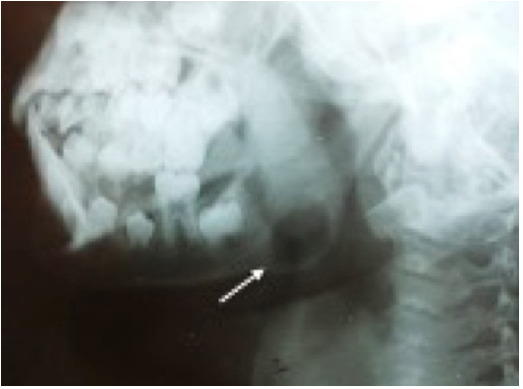

Based on the clinical data and medical history, the maxillofacial surgeon indicated a lateral skull radiograph (Figure 2), where atypical bone lysis was observed according to the age of the patient. Then a computed tomography was requested to determine the limits and three- dimensional characteristics of the lesion, where cortical expansion with bone lysis was observed Figure 3), which led to a presumptive diagnosis of a malignant tumor in the mandibular angle to be determined, also laboratory tests were requested showing increased levels of alkaline phosphatase (212 U/l), serum phosphatase (6.9 mg/dl) and serum calcium (10.7 g/dl). According to clinical, imaging and laboratory examination, the maxillo- facial surgeon performed incisional biopsy in June of 2019. The patient underwent general anesthesia with orotracheal intubation, carried out via an intraoral approach with an incision in the left anterior border of the mandible branch dissecting to the mandibular angle of the external fase and performing an ostectomy with a low-speed handpiece at the site of the lesion, bone tissue was obtained for histopathological analysis.